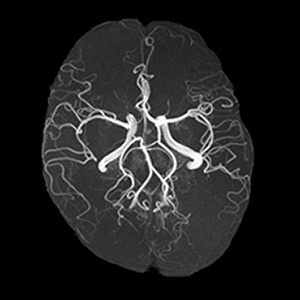

MRI

Magnetic Resonance Imaging

核磁気共鳴画像

MRI(Magnetic Resonance Imaging)とは

核磁気共鳴画像と言い、磁石と電磁波を

利用し様々な方向から体内を撮像できる装置です。

X線を使用しないため被曝が無く、頭部や心臓、腹部、整形領域など様々な部位の撮像が可能です。特に急性期の脳梗塞や頭の小さな出血を映し出すのに非常に有効です。また、造影剤を使用せず頭部や下肢などの血管の形態や流速を映し出すことも可能です。MRIは強力な磁石でできているため金属吸着や火傷、ペースメーカーの誤作動など様々な危険を伴います。安全に検査を行うため、検査前に確認書への正確な記入をお願いします。また入室前にも確認をさせていただきますのでご協力をお願いいたします。